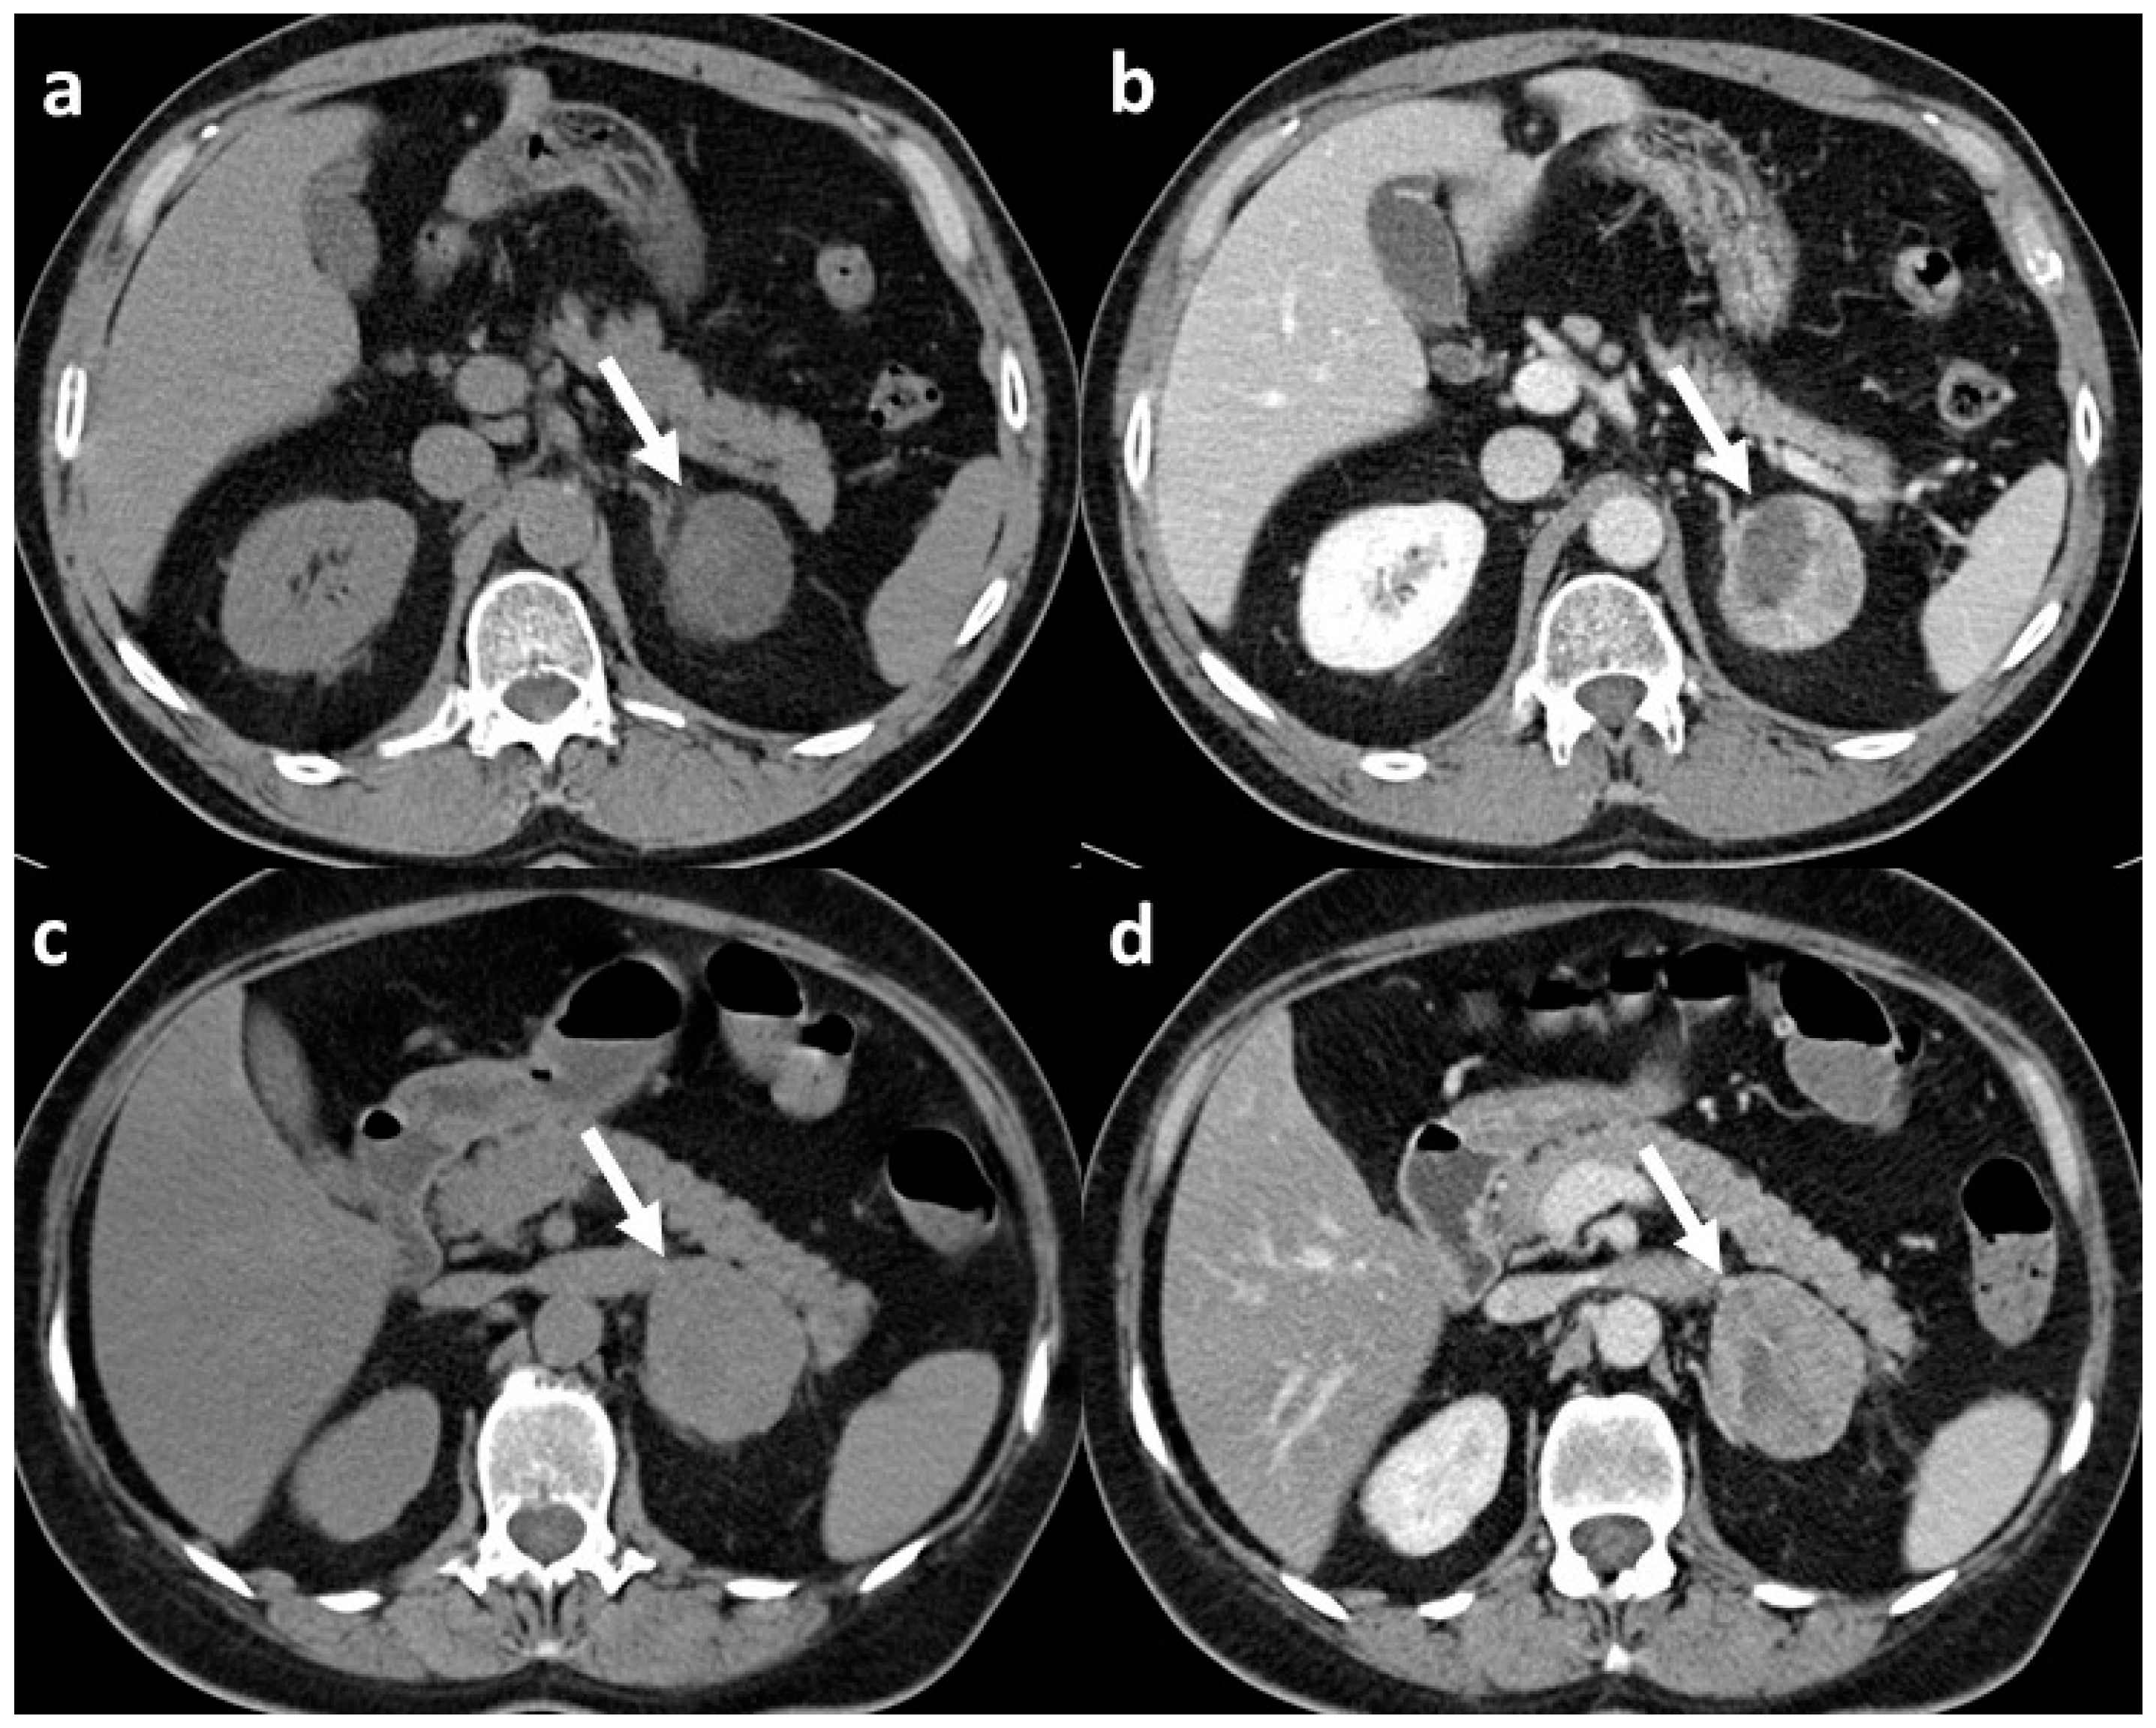

Focusing on the two studies that compared adrenal adenoma and adrenocortical carcinomas, the results showed a very good performance of the CT texture analysis in differentiating benign from malignant lesions, with an AUC of 0.86 reported by Elmohr et al. [17] and an accuracy of 93% reported by Torresan et al. [21] (Figure 1 and Figure 2).

Figure 1.

CT scans of adrenal adenoma and adrenocortical carcinoma both with CT features suspect for malignant lesion: (a) unenhanced scan of histopathologically confirmed adrenal adenoma (arrow) with mean densitometry of 22 HU; (b) venous phase scan of the same adrenal adenoma (arrow), at late scan (not shown) the relative washout of contrast medium was <40%; (c) unenhanced scan of histopathologically confirmed adrenocortical carcinoma (arrow) with mean densitometry of 28 HU; (d) venous phase scan of the same adrenocortical carcinoma (arrow), and also in this case, at late scan (not shown), the relative washout of contrast medium was <40%.